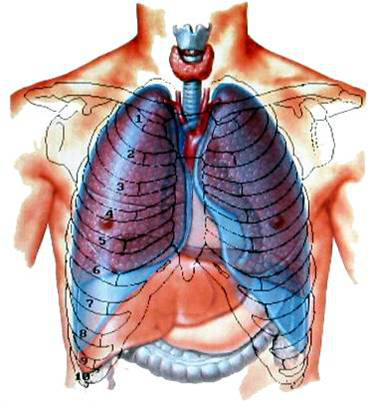

在图片中我们看到的蓝色组织构成的就是胸膜腔,从图片中我们可以明显看到胸膜腔,左右分割,左边是左边,右边是右边,互不相通,两胸膜腔之间的心脏和气管构成了纵隔。

开放性气胸时,如果右侧胸膜腔有开放性伤口,则右侧胸膜腔内负压的消失,肺组织完全萎缩,就好像往右侧肺组织充气一样,气管和纵隔就被推向了左侧(也就是健侧)。

还是这个人,右侧开放性气胸,右侧胸膜腔内的压力几乎等于大气压,所以,右侧胸膜腔内压力不会随着呼吸上下波动;但是,左侧胸膜腔是正常的,左侧胸膜腔内压力会随着呼吸上下波动。